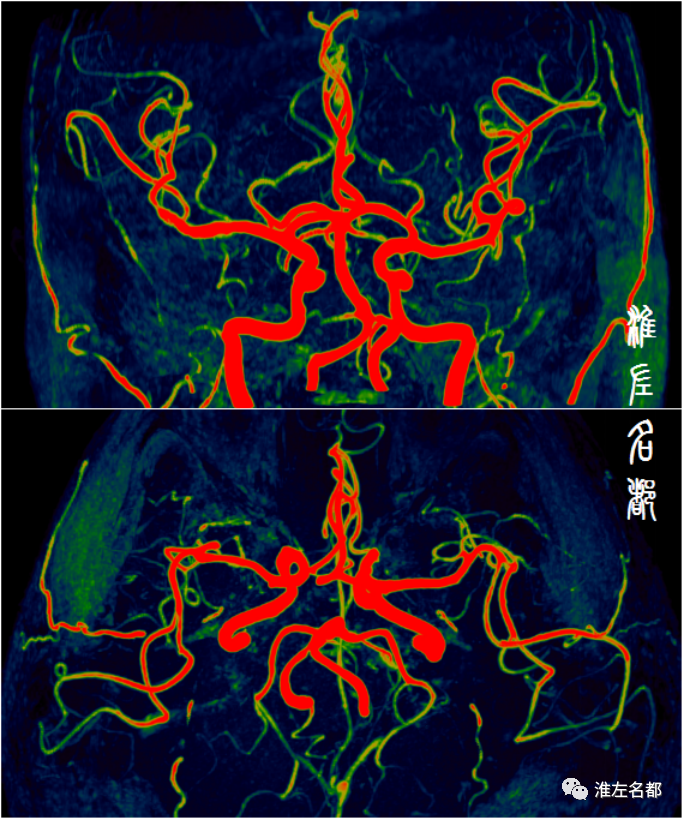

脑供血动脉系统解剖复杂,按管径来说,分为大血管、中血管和小血管;以颅骨为界,分为颅外和颅内脑动脉;以硬脑膜为界,分为硬膜内和硬膜外动脉。按脑供血区的差异,分为前循环和后循环脑动脉,前循环又分为左右两侧,前后循环和左右前循环通过WILLIS环相连接。当主要脑动脉发生严重狭窄或闭塞病变时,WILLIS环是相当重要的侧支循环代偿途径,然而其存在诸多变异。

伴随科技发展,近半个世纪以来,多种先进技术,尤其是血管影像技术,被应用于脑血管病变的诊断评估,极大促进了该领域的发展。目前常规应用于脑血管病变评估的影像技术包括:DSA、CTA和MRA,这些技术主要通过显示血管腔的异常进行血管病变的评估,如狭窄、闭塞、动脉瘤、血管畸形等病变,其中以DSA的诊断准确性最高,常被奉为“金标准”,缺点是有创操作,有潜在风险。